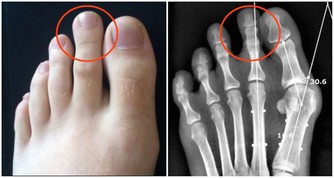

邱大姐,今年64歲。半年前,她出現頭暈、乏力,到醫院檢查,有嚴重的貧血。前段時間病情加重,又到省立醫院就診,發現白細胞、血小板均有減少,進一步檢查確診為「骨髓增生異常綜合症」。

這個病名很專業,可能很多非血液科的醫生都沒聽到過。說直白點,就是患者的造血幹細胞惡性克隆,導致無效造血。白血病,我們通常稱之為血癌,骨髓增生異常綜合征其實也是一種血液腫瘤。這種病預後很差,有30%左右的患者會發展為白血病。

「5年前,這種病很少,近幾年出現爆發性增長。」血液科副主任說,昨天住在醫院的49個病人中,有10人是骨髓增生異常綜合征,在5年前估計只有一兩個。